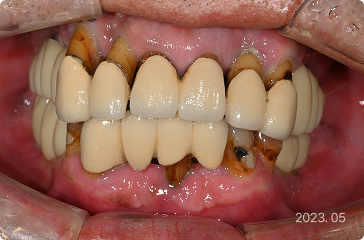

59세, 남 ㅣ 앞니 임플란트

“앞니 뿌리가 다 보여서 보기에 너무 안 좋아요.”

치료 전

원데이 임플란트

치료 후

• 앞니 뼈 흡수 및 뿌리 과다 노출

• 원데이 임플란트로 잇몸 및 치아 형태 복구

• 발치,식립 > 최종 보철 약 2개월 내 완성